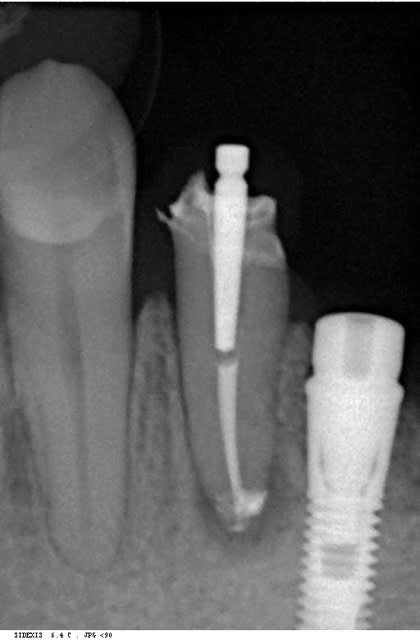

un cas comme je les aime......

bon, une petite pensée pour mon pote athos.....

Maintenant ce9ajl - Eugenol

Images 1 qtgoxf - Eugenol